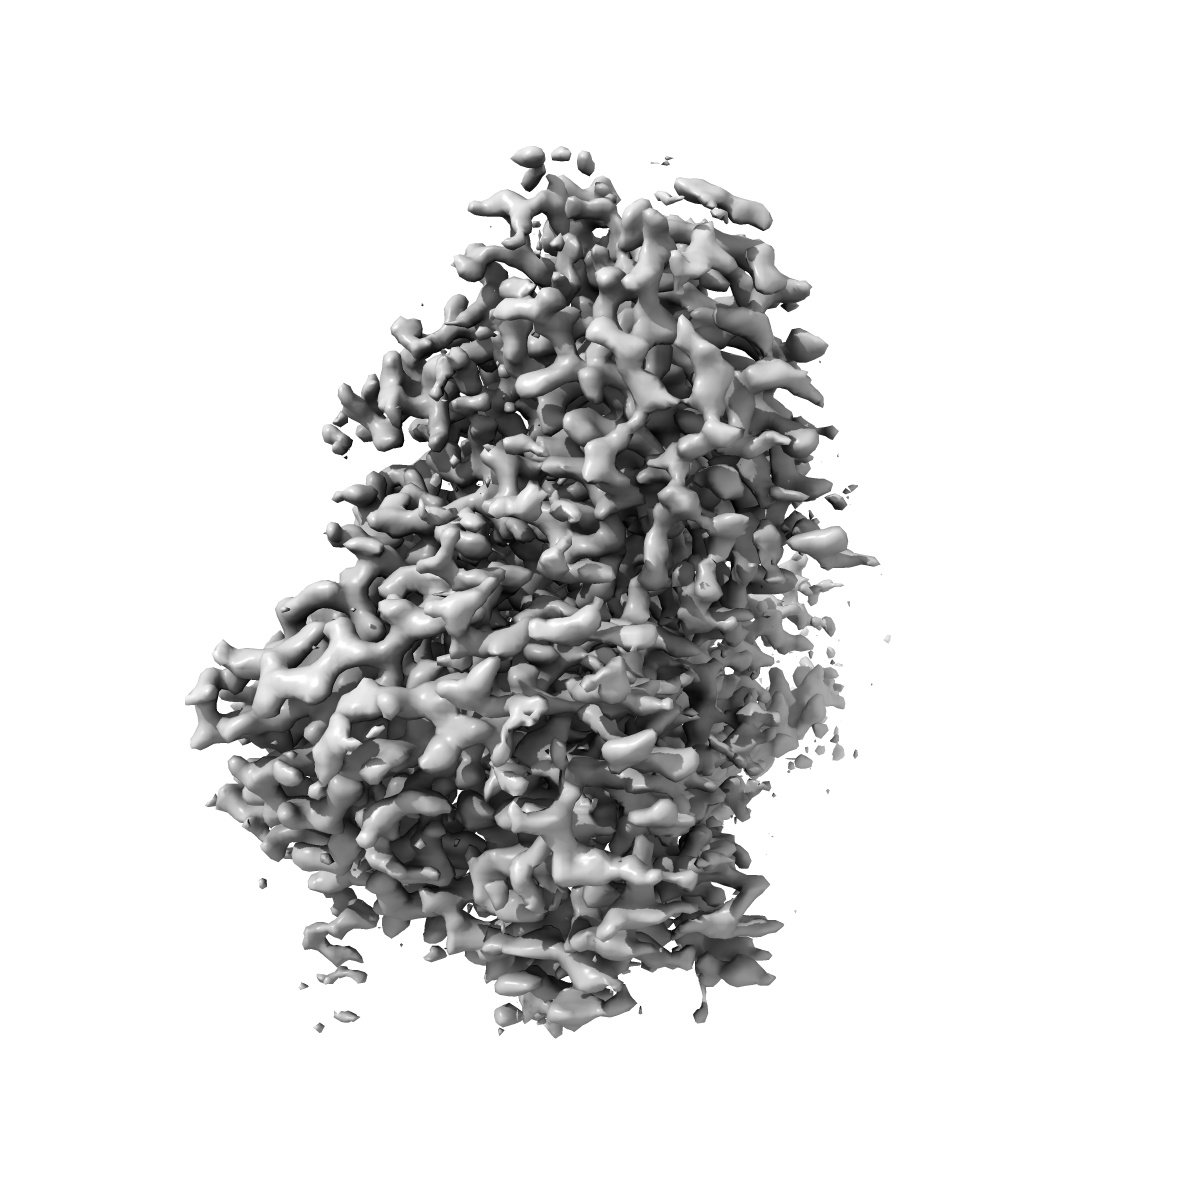

Human Amylin1 Receptor in Complex with Gs and human Calcitonin Gene-Related Peptide

Sample: Human Amylin 1 Receptor in complex with Gs and human calcitonin gene-related peptide

Fitted models: 9auc

Cryo-EM Structure of the Human Amylin 1 Receptor in Complex with CGRP and Gs Protein.

Cao J , Belousoff MJ , Danev R , Christopoulos A, Wootten D , Sexton PM

(2024) Biochemistry , 63 , 1089 - 1096

PUBMED: 38603770

DOI: doi:10.1021/acs.biochem.4c00114